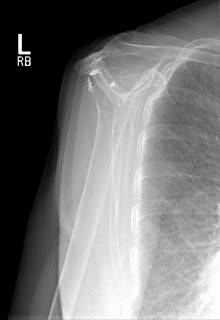

The x-rays below are from a different patient but the operation was by the same surgeon. In this patient, there is moderate pain because the anchors remain in the bone. The repair has failed. If you look carefully, you can see that the head of the humerus (the bone with the metal anchors) has moved upwards and now is touching the bone above it (the acromion). This can only happen when there is a massive rotator cuff tear. Once again, no MRI needed. This patient cannot lift her arm at all and has what we call a pseudoparalyitc shoulder.

This patient is considering a reverse should arthroplasy. She is the same age as the first patient but much more active. I suspect she would do well with the new shoulder.